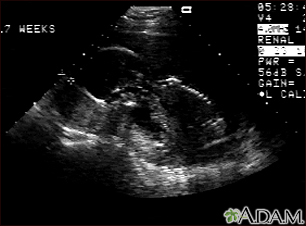

Ultrasound, normal fetus - profile view